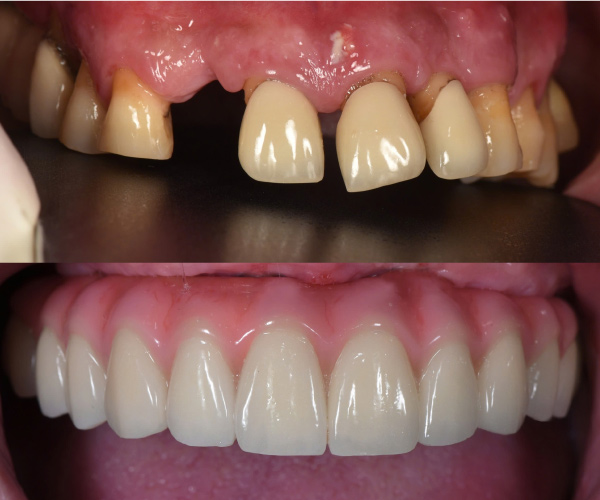

Tiến sĩ, Bác sĩ Võ Văn Nhân với hơn 23 năm kinh nghiệm trong lĩnh vực Implant Nha khoa, đã thực hiện thành công hơn 20.000 ca cấy ghép răng Implant từ đơn giản đến phức tạp. Những thành tựu đặc biệt mà Ts.Bs Võ Văn Nhân đạt được góp phần mang lại nụ cười hạnh phúc, mở ra cơ hội cho rất nhiều trường hợp mất răng, không răng bẩm sinh.

Cấy ghép implant phục hồi toàn diện chức năng nhai và thẩm mỹ cho người bị nha chu nghiêm trọng, người mất răng toàn bộ và người cao tuổi nhiều bệnh nền.